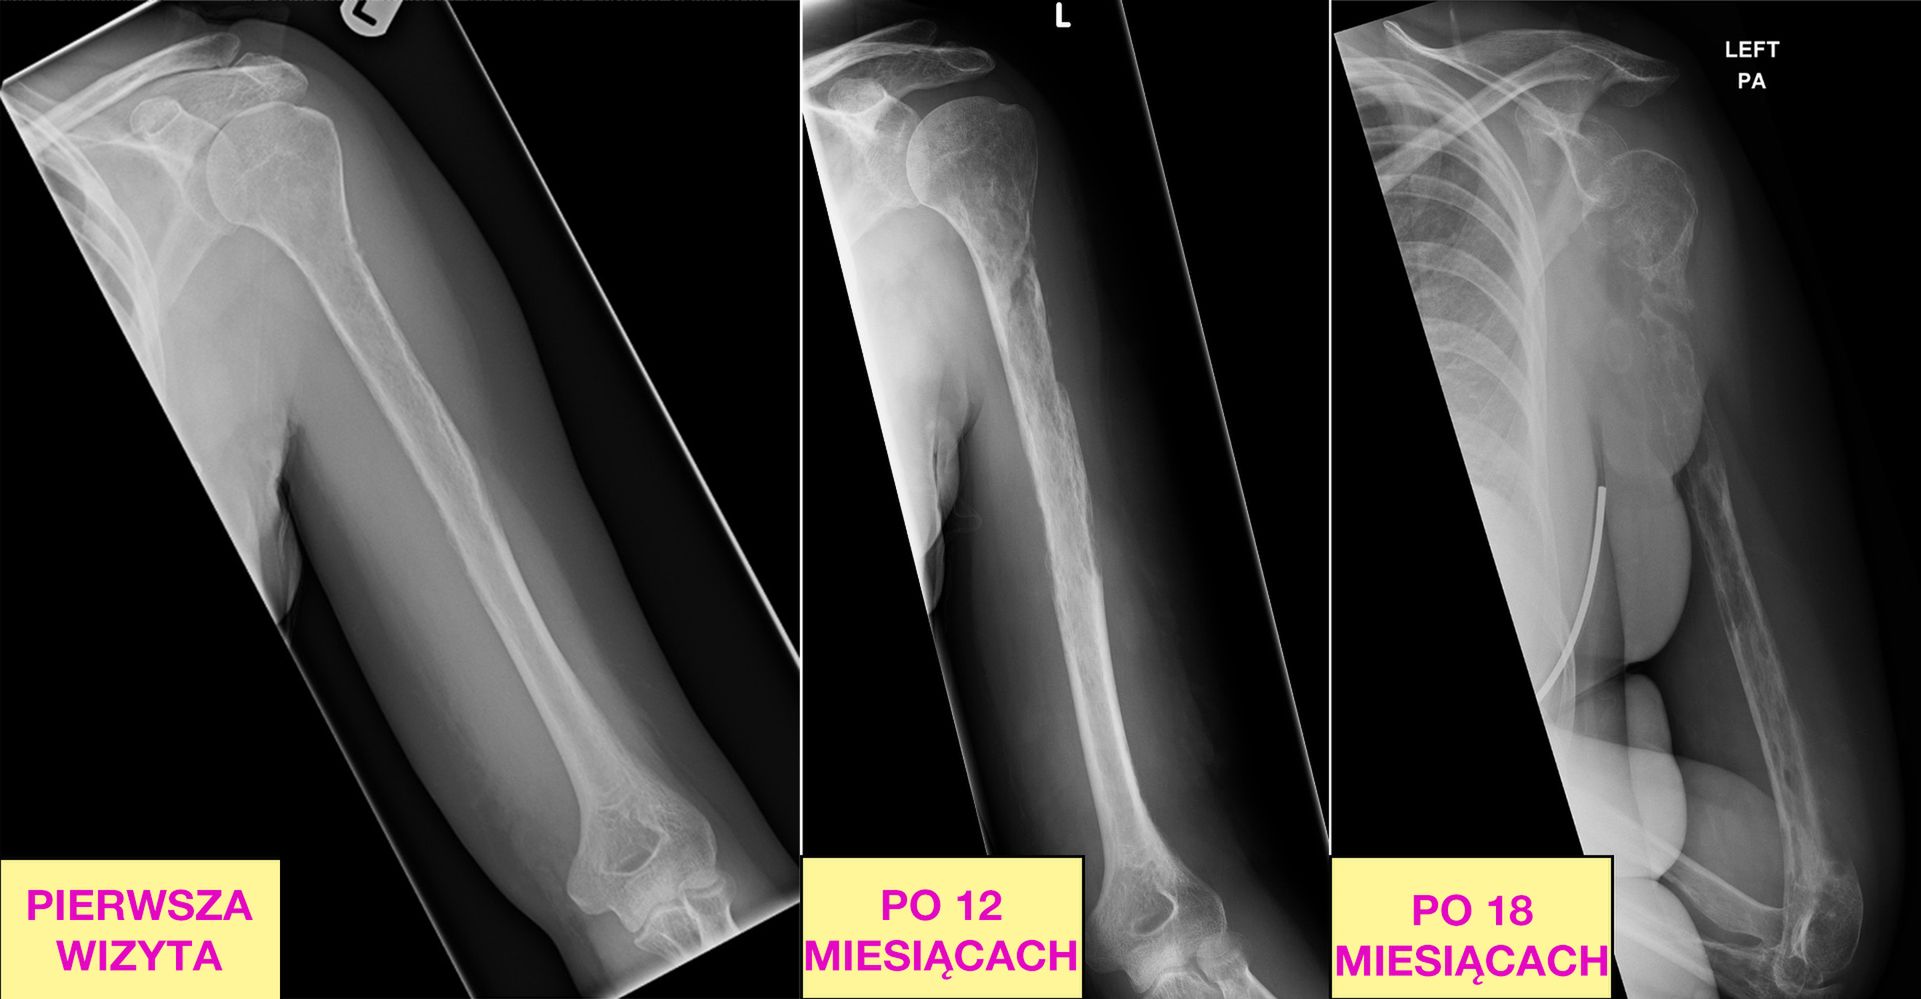

Szokujące zdjęcia rentgenowskie z kolejnych wizyt pacjentki pokazują proces, w którym kości znikają niemal na oczach lekarzy.

Ciesząca się wcześniej dobrym zdrowiem 44-latka zgłosiła się do ortopedy. Bolała ją lewa ręka od łopatki po łokieć. Pierwsze prześwietlenie wykazało zmiany chorobowe na głowie kości ramiennej. Sądząc, że to rak, lekarze z Edynburga poddali ją biopsji. Ta nie wykazała żadnych zmian nowotworowych. Dopiero po trzeciej, wykonanej dwa miesiące później odkryto łagodne zmiany typowe dla gojenia się kości.

Po kolejnych 10 miesiącach wróciła do lekarza. Ból nie ustępował, doszła opuchlizna. Badania radiologiczne wykazały kolejne zmiany naczyniowe w innym miejscu. Biopsja kości i okolicznych tkanek pokazała obecność osteoklastów. To komórki zdolne rozpuszczać i wchłaniać tkankę kostną. Są ważne dla organizmu w trakcie kształtowania się kości czy procesu gojenia złamań. W nadmiarze prowadzą do osteoporozy. U 44-letniej pacjentki dosłownie "pożerały" kość ramienną.

W kolejnych miesiącach proces rozszerzył się. Znikać zaczęła kość łokciowa lewej ręki. Wówczas lekarze nie mieli już wątpliwości i postawili, szokującą nawet dla nich, diagnozę. Kobieta cierpiała na chorobę Gorhama-Stouta, zwaną czasem "chorobą znikających kości". Opisujący ten przypadek dr Jarrad Stevens wspomina, że medycyna zna jedynie 63 takie przypadki. Opisano ją po raz pierwszy w 1954 roku.